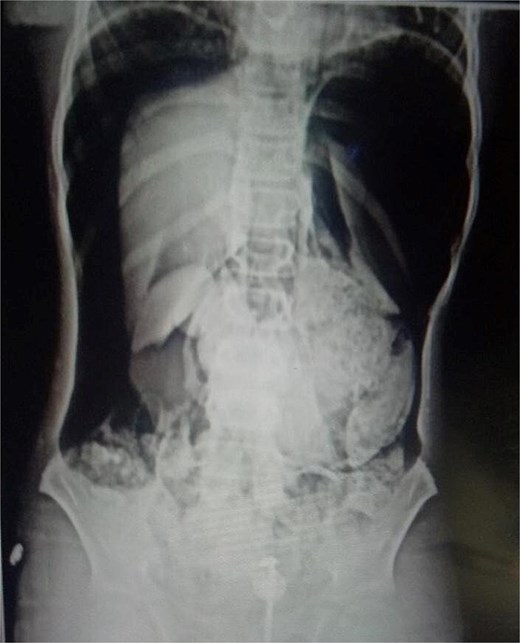

On arrival, he was alert but visibly distressed due to pain. His vital signs were stable initially, but on examination, he had signs of generalized peritonitis with tense, diffusely tender abdomen in all quadrants and absent bowel sounds. Digital rectal examination was unremarkable. Initial laboratory investigations showed a total leukocyte count of 9.3 × 103/μl and platelet count of 143 × 103/μl. A plain abdominal X-ray demonstrated massive pneumoperitoneum (Figs 1 and 2), strongly suggestive of hollow viscus perforation. Based on clinical and radiological findings, a provisional diagnosis of hollow viscus perforation was made.